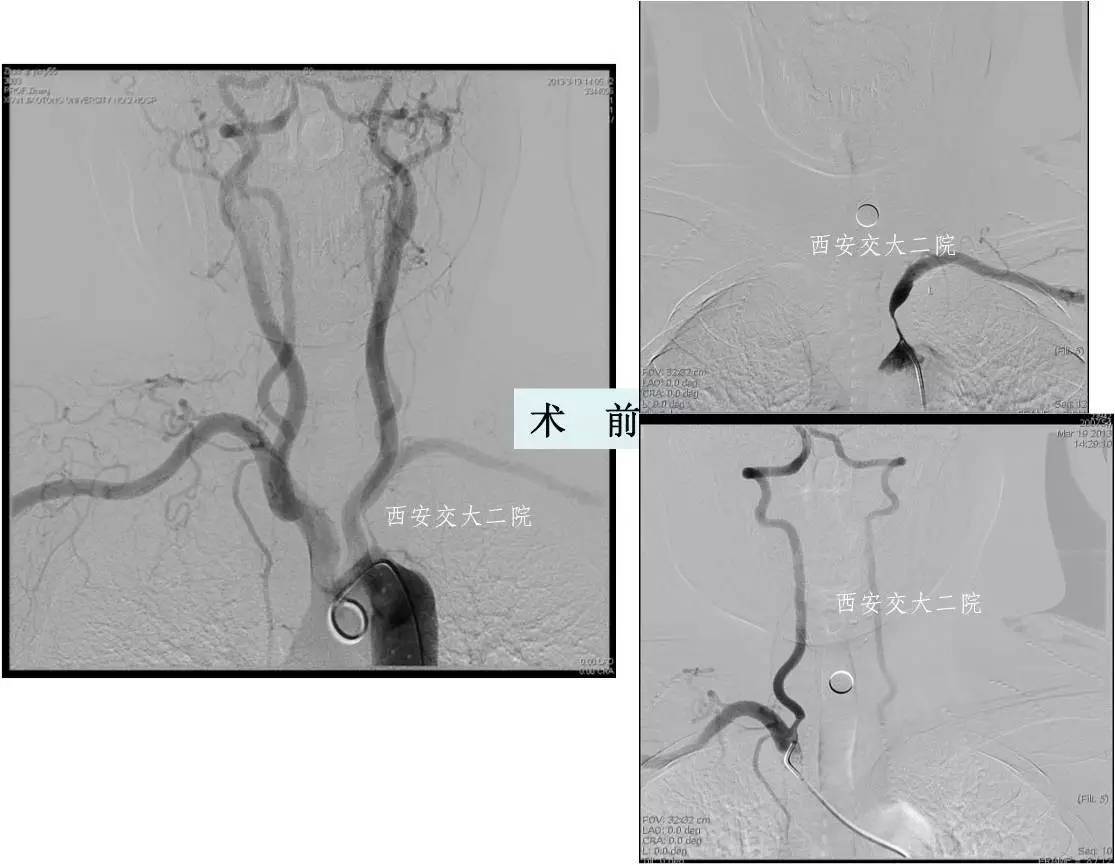

病后2小时DSA示左颈内动脉眼段闭塞。

取栓后即刻脑CT及临表

术后24h脑CT及临表

术后4天脑CT及临表

术后2周脑CT及临表